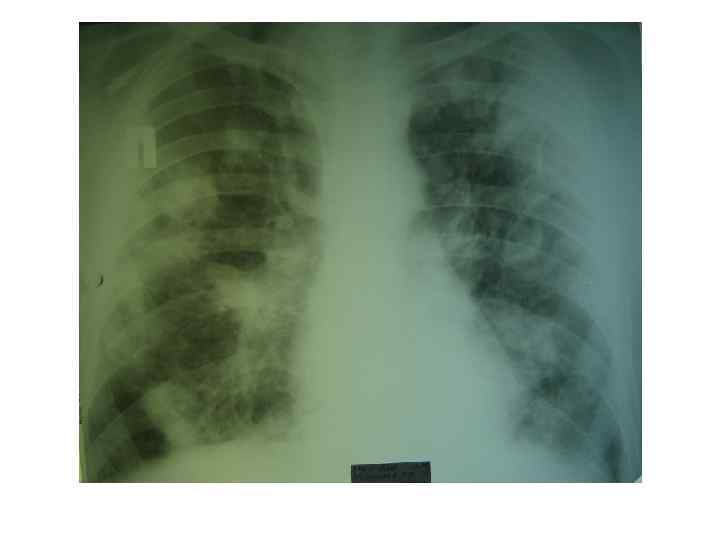

Поражение легких при ИЭ трикуспидального клапана у наркоманов • Синдром септической эмболии легочной артерии 90, 9% (65 -100%) • Синдром острого повреждения легких, острый респираторный дистресс-синдром 12, 5% (13, 2% ) • Пневмония, вызванная Pneumocystis carinii у наркоманов больных СПИД В. И. Уланова, В. И. Мазуров 2007

Осложнения септической эмболии легочной артерии при ИЭ правых отделов сердца • Инфильтративные изменения в легких выявляются рентгенологически у 83 %¹ (55100%)² • 1 по нашим наблюдениям • 2 по данным литературы (В. И. Уланова, В. И. . Мазуров 2007; Zuo L, Guo S, Rong F 2001; Karchmer A. W. 2005; Zuo LE, Guo S. 2007; Moss R, Munt B. 2003; Remetz MS, Quagliarello V 1992; Robbins MJ, Soeiro R, Frishman WH et al. 1986. ) • Абсцесс легких; • Плевральный выпот; • Эмпиема плевры; • Инфаркт легких; • Легочное кровотечение; • Пневмоторакс; • Микотическая аневризма легочной артерии

Рентгенологические признаки СЭЛА при ИЭ • двустороннее поражение; • наличие множественных небольших, нечетких округлых или овальных теней различных размеров (у 68% ), очаговых инфильтратов (у 54%) и клиновидных теней (у 22%) расположенных чаще всего в периферических зонах легких или субплеврально; • склонность к распаду инфильтратов с возникновением абсцессоподобных полостей (у 50%) и кист (у 81%); • быстрая динамика появления новых инфильтратов и медленное обратное развитие с длительным сохранением кистовидных тонкостенных полостей; • возможно развитие плеврального выпота (у 50%) и редко пиопневмоторакса. По данным Zuo LE, Guo S. (2007)

Руководство по ИЭ Европейского общества кардиологов 2004: Множественные быстро меняющиеся легочные инфильтраты вызывают подозрение на ИЭ правых отделов сердца

ИЭ трикуспидального и митрального клапана с легочными и системными эмболиями у инъекционного наркомана 21 года. N. Martinelli et al European Heart Journal 2006 27(24): 2938